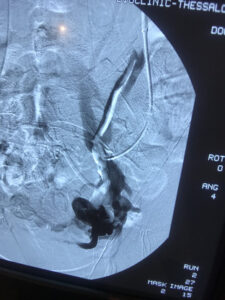

Η θεραπεία εκλογής για το σύνδρομο πυελικής συμφόρησης είναι η ενδαγγειακή αποκατάσταση με τη χρήση ελασμάτων (coils). Ουσιαστικά, πρόκειται για μια ελάχιστα επεμβατική μέθοδο, που αποσκοπεί στην κατάργηση των προβληματικών φλεβών με αρκετά ικανοποιητικά αποτελέσματα. Πρόσφατα, δημοσιεύτηκε στις κατευθυντήριες οδηγίες της Αγγειοχειρουργικής κοινότητας και στο Αμερικάνικο φλεβολογικό Forum, ως προτεινόμενη θεραπεία για την αντιμετώπιση της νόσου , η ενδαγγειακή αποκατάσταση με εμβολισμό.

case 2

φλέβας με ύφεση συμπτωματολογίας